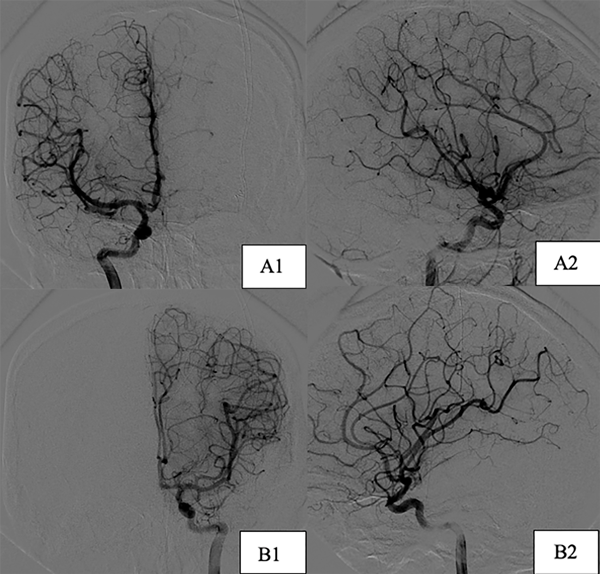

Paciente de sexo femenino, de 17 años, sin antecedentes patológicos, a quien en contexto de estudio por episodio de crisis comiciales de novo se le diagnostican dos MAVs supratentoriales, una frontal derecha de 25 x 29 mm diámetro, con aferencias silvianas, de nido compacto y drenaje hacia el seno longitudinal superior a través de gran vena cortical y otra temporal izquierda de 16 x 11 mm con aferencias silvianas, de nido compacto y drenaje hacia el seno transverso, sin evidencia de signos sugestivos de sangrado (Figura 4). Se decidió estudiar y descartar síndromes congénitos para luego programar la cirugía. Debido a que ninguna de las dos lesiones presentaba factores angiográficos de rotura y por su localización en el hemisferio no dominante se decidió abordar inicialmente la malformación frontal derecha (Figura 5) y 7 meses después se realizó la exéresis de la restante con control angiográfico postquirúrgico satisfactorio y ninguna complicación asociada (Figura 6).

Figura 6. Imágenes postoperatorias caso 2. Incidencias derechas. A1) Corte coronal. A2) Corte sagital. B) Incidencias izquierdas. B1) Corte coronal. B2) Corte sagital.